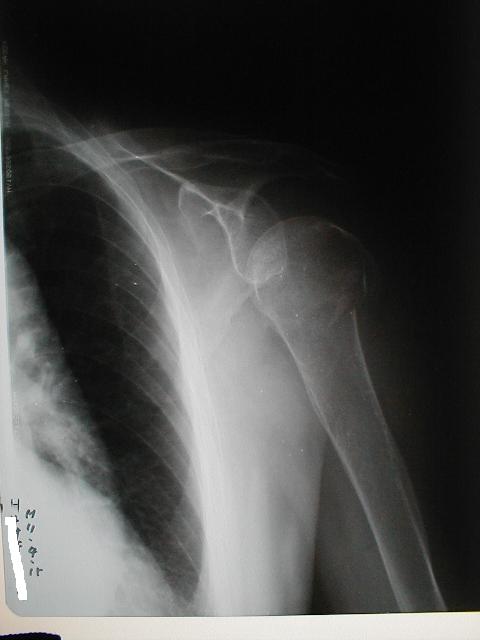

症例1

上腕骨頚部(外科)骨折と肩関節脱臼の合併症例

66歳 女性

左上腕骨頚部(外転)骨折

左肩関節脱臼